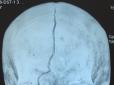

Шансів, що виживе, майже немає: В Одесі злодій проломив бабці голову через... 100 грн

1 квітня в Одесі грабіжник проломив бабусі засновника онлайн-радіостанції RADIO MORE.FM Павла Козлова голову. Про це він написав на своїй сторінці в facebook, передають Патріоти України.